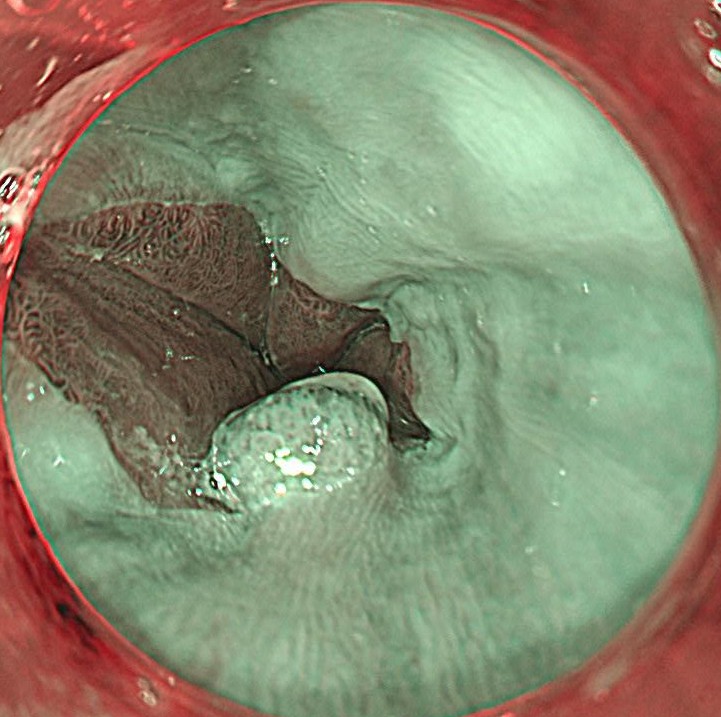

狭帯域光 (NBI) 観察しますと、腫瘍血管は認めず、良性の炎症性ポリープと診断しました。有症状であり、また今後のがん化のリスクも否定できない (エビデンスレベルは低いですが) ため、治療対象と判断しました。